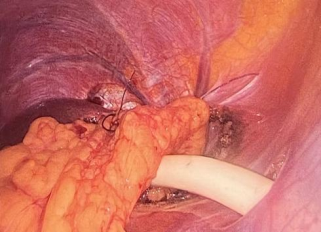

大网膜填塞死腔:随后用带蒂大网膜填塞囊腔死区,像加了层“防护垫”,防止膈肌与肝脏粘连;

镰状韧带固定引流:最后经镰状韧带置管持续引流,确保囊腔无积液愈合,既保留了腹腔镜微创、创伤小、恢复快的优势,又弥补了传统手术的不足。